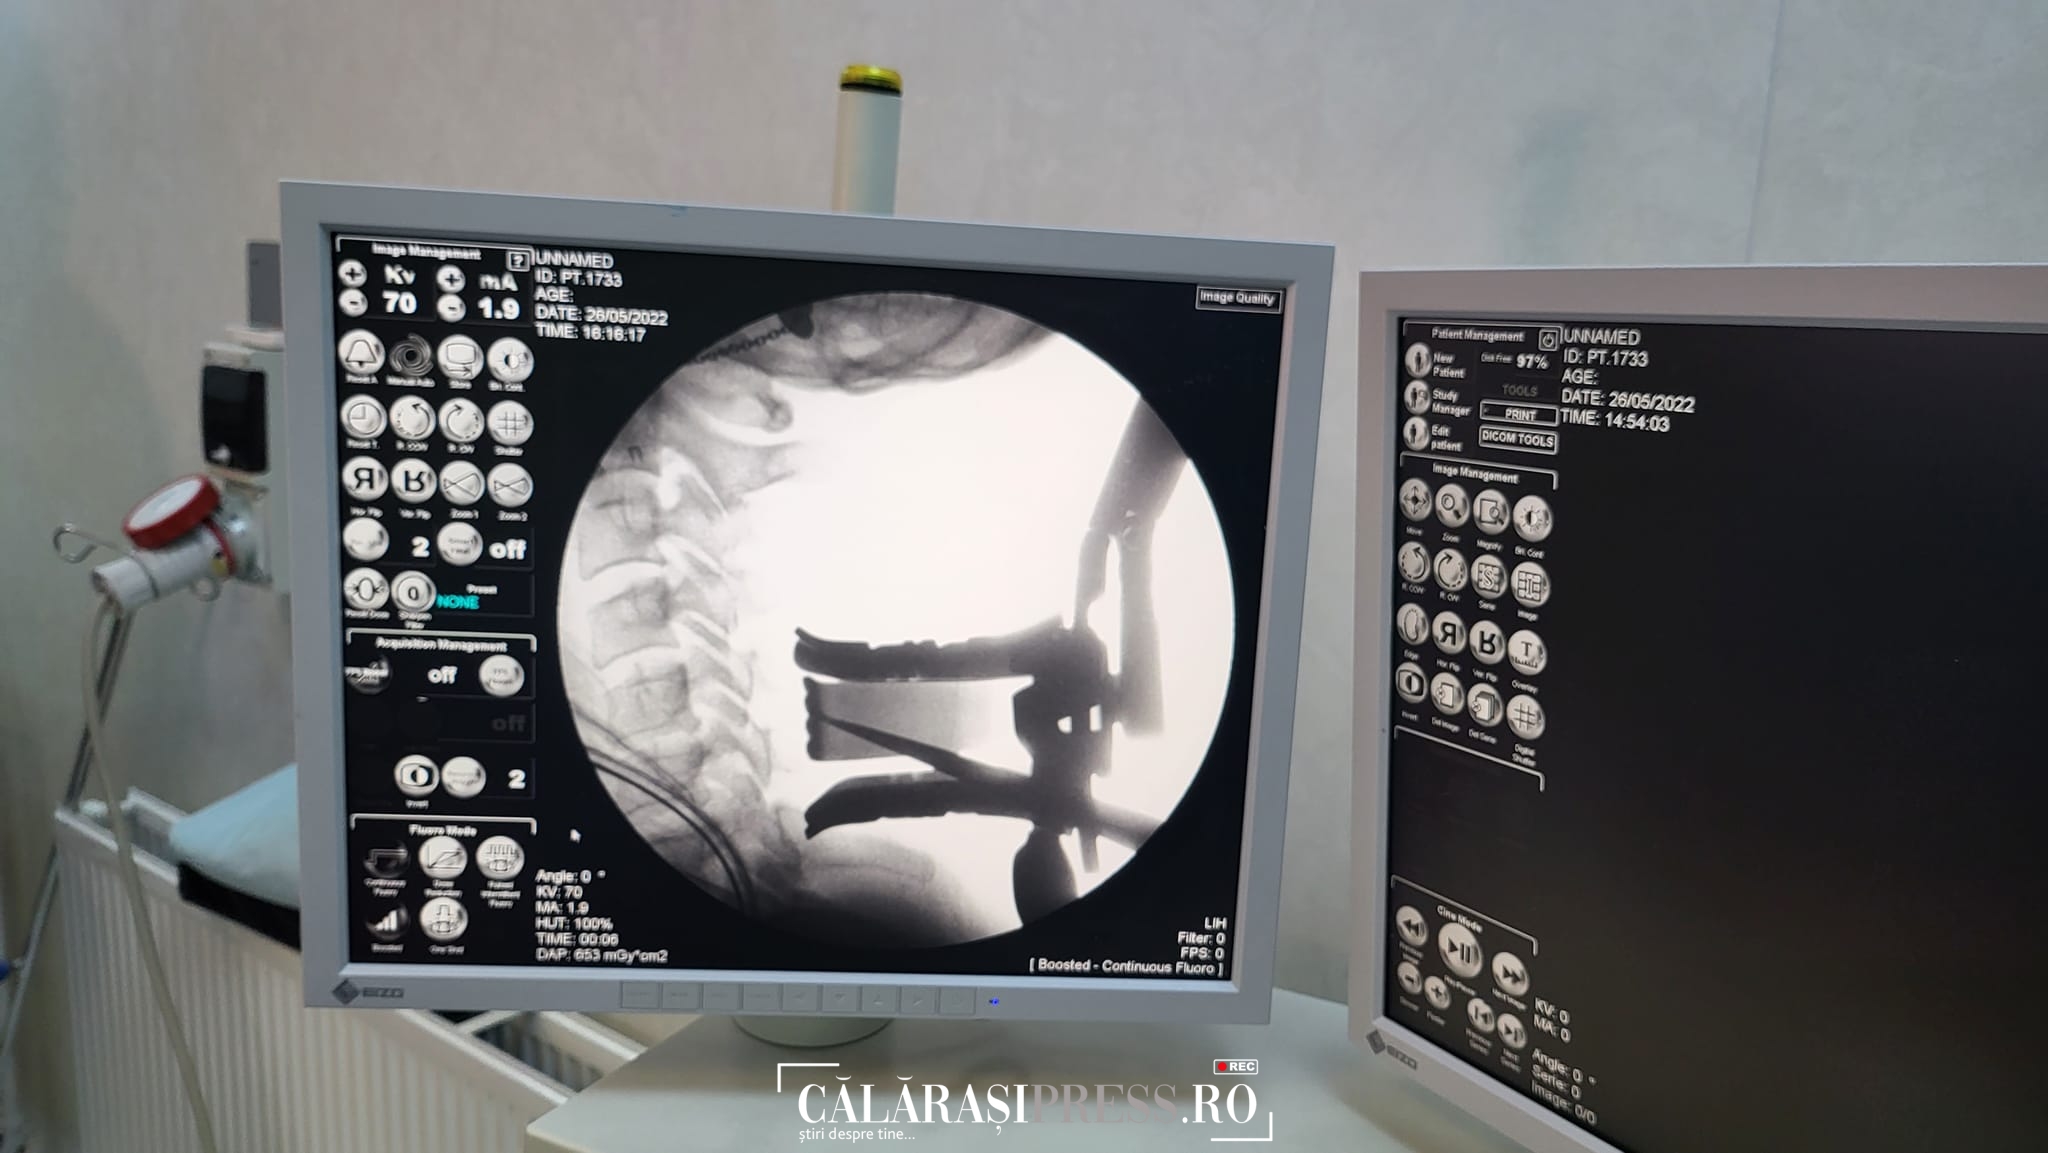

Prima operație de hernie cervicală, realizată la Călărași